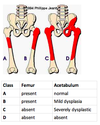

What is the evidence for screening DDH

No evidence to screen

Imaging prior to 6 months in infants with clinical evidance, fam hx, breech,